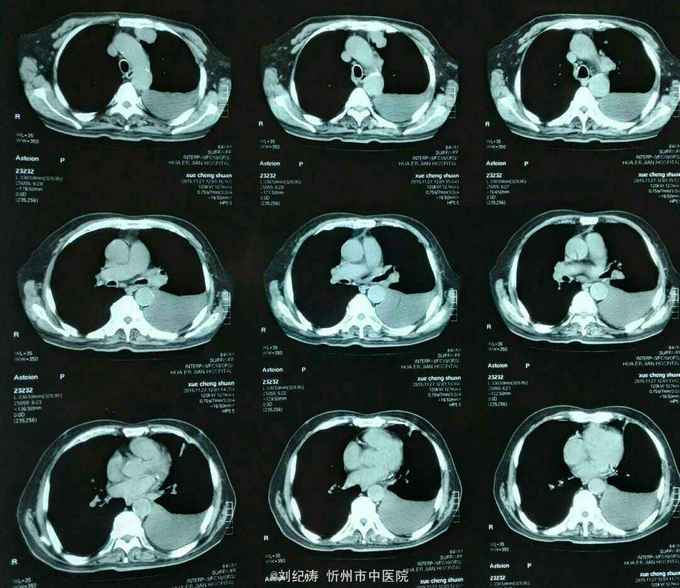

查体:ECOG评分:3分,生命指征平稳,浅表淋巴结未触及明显肿大,双眼睑无水肿,唇无发绀,颈软,双侧胸廓对称,左肺语颤增强,左肺呼吸音消失,右肺呼吸音粗,可闻及哮鸣音,心律齐,腹平软,肝脾肋下未触及,移动性浊音阴性,肠鸣音3次/分,双下肢无水肿。 辅助检查:血常规(2016.1.1):WBC:10.6*109/L,RBC:4.69*1012/L, PLT:165*109/L ,HGB:167g/L.生化(2016.1.1):谷丙转氨酶11U/L,谷草转氨酶11U/L,总蛋白60g/L,白蛋白33g/L,尿素:9.8mmol/L,肌酐:123umol/L,尿酸:251 umol/L,血糖:7.37 mmol/L;电解质:钾:4.79mmol/L,钠:123.5 mmol/L,氯:85.7 mmol/L,钙:2.03 mmol/L。肺部CT(2016.1.1):左肺完全萎缩,左侧胸腔大量积液,右肺未见异常,纵膈轻度右移,未见明显肿大淋巴结。

现患者胸腔引流血性胸水2000ml,症状略有改善;为进一步控制胸水、控制肿瘤进展,拟行胸腔药物灌注,由于患者高龄,大家讨论下灌注什么药比较合适?另有无口服依托泊苷指征?